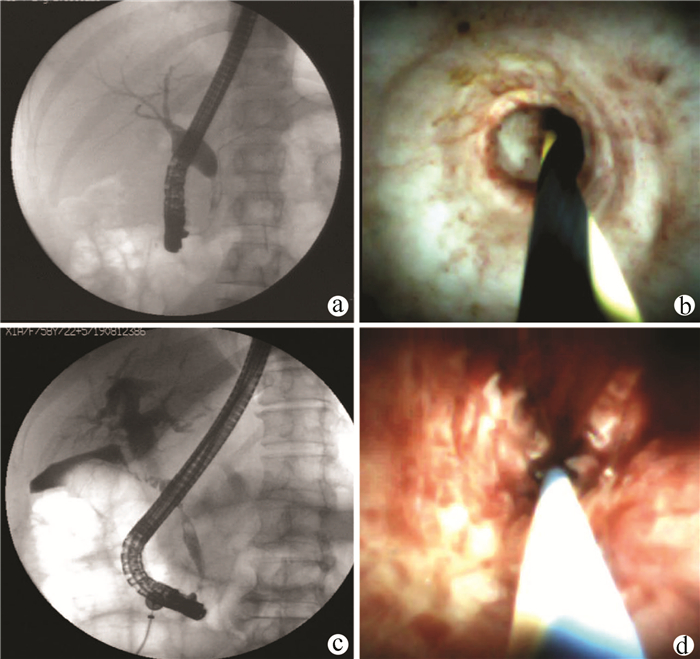

2.2 SpyGlass系统在胆管狭窄中的诊断情况

共44例胆管狭窄的患者进行SpyGlass胆道镜系统诊断,所有患者均行狭窄处球囊扩张,放置胆管或胰管支架的患者有23例(52%)。44例胆管狭窄的患者中,16例术中直视下考虑为炎性狭窄,表现为胆管内表面结构光滑、呈细颗粒样、无新生血管或肿块、表面发白并呈皱襞样集中;28例术中直视下考虑为恶性狭窄,表现为胆管内结节样或乳头状隆起、表面见扭曲扩张或粗细不均的血管、易自发性出血。共有33例患者行胆道镜直视下(SpyBite)活检,术后病理提示:良性病变12例,恶性病变20例,恶性病变的患者有8例经过外科手术病理证实,此外,1例患者因术中病变组织取材不充分,在随访过程中出现与恶性肿瘤相一致的疾病进展(肿瘤指标持续性升高及肿块持续性增长),诊断为恶性狭窄。在对11例未取活检患者的随访过程中,2例患者后续行外科手术治疗,术后病理为壶腹部中低分化腺癌和胆管绒毛状腺癌,1例患者在随访过程中影像学资料证实为转移性肿瘤,其余患者在随访过程中均未发现狭窄处进展。SpyGlass视觉印象的诊断敏感度为92%(24/26),特异度为94%(17/18),准确度为93%(41/44),SpyBite直视活检的诊断敏感度为71%(15/21),特异度为92%(11/12),准确度为79%(26/33)。图 1展示胆管良恶性狭窄的SpyGlass镜下图片。视频1和2(附录1和2)分别展现良性和恶性胆管狭窄的镜下过程。